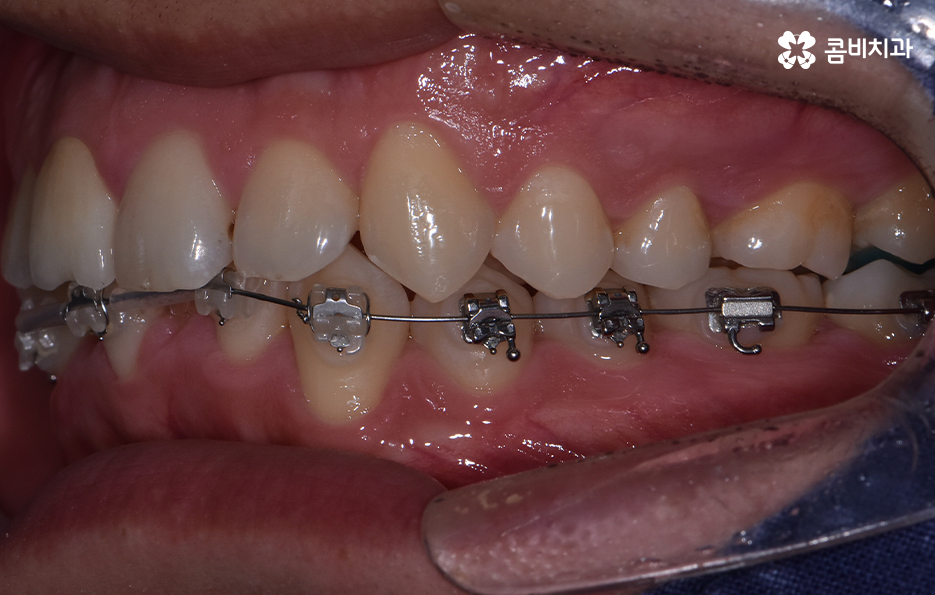

하지만 위에 보시는 환자분의 사례는 윗니와 아랫니의 교합을 고려하고 얼굴형, 골격 등을 고려했을 때도 아랫니만 교정이 가능했던 사례인데 일반적으로 윗니가 아랫니를 살짝 덮고 있어야 하는데 아랫니의 앞니 부분이 유독 안으로 들어와 있었기 때문에 아랫니교정 만으로도 치아교정이 가능했던 사례라고 보시면 좋을 거예요

위 환자분의 사례로 보면 아랫니 중에 하나가 유독 앞으로 튀어나와 있고 나머지 치아는 안으로 들어가 있기 때문에 교합으로 따져볼 때는 아랫니를 전체적으로 앞으로 이동시켜야 했기 때문에 비발치로도 충분히 교정이 가능했고 아랫니교정 만으로도 치료가 가능했어요